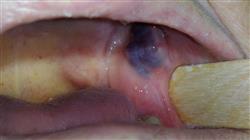

Для изучения гортани необходимо знать прикладную анатомию глотки и гортани, а также ее физиологию. Клиническое обследование гортани включает аспекты, связанные с наличием структурных и/или функциональных изменений, относящихся к трем функциям гортани, с использованием методов, которые в последнее время усовершенствовались благодаря эндоскопическим и компьютерным системам визуализации.

- Глубоко изучить анатомические и функциональные характеристики ротовой полости и глотки, а также шейного отдела пищевода, применительно к глотанию, и физиопатологию нарушения глотания. Изучить эпидемиологию и группы риска, а также этиологию дисфагии Изучить клинические аспекты дисфагии и ее осложнений и научитесь исследовать нарушения глотания клинически и инструментально В завершении, изучить медицинское, реабилитационное, диетическое и хирургическое лечение дисфагии

На нашем Университетском курсе вы узнаете об анатомии и физиологии полости рта и глотки, о различных нарушениях глотания и методах оценки и диагностики, используемых при их выявлении. Вы также узнаете о терапевтических стратегиях лечения этих расстройств, включая реабилитационные упражнения и использование вспомогательных технологий. Наша команда преподавателей состоит из профессиональных экспертов в области медицины и терапии расстройств глотания, которые будут сопровождать вас на протяжении всего курса и отвечать на все ваши вопросы. По окончании Университетского курса вы будете готовы оказывать качественную помощь пациентам с расстройствами глотания, помогая улучшить качество их жизни и самочувствие. Кроме того, вы будете обладать необходимыми навыками для проведения научных исследований в этой области и внесения вклада в развитие медицины. Не упустите эту возможность: поступите в TECH Технологический университет и измените ситуацию в сфере здравоохранения к лучшему!